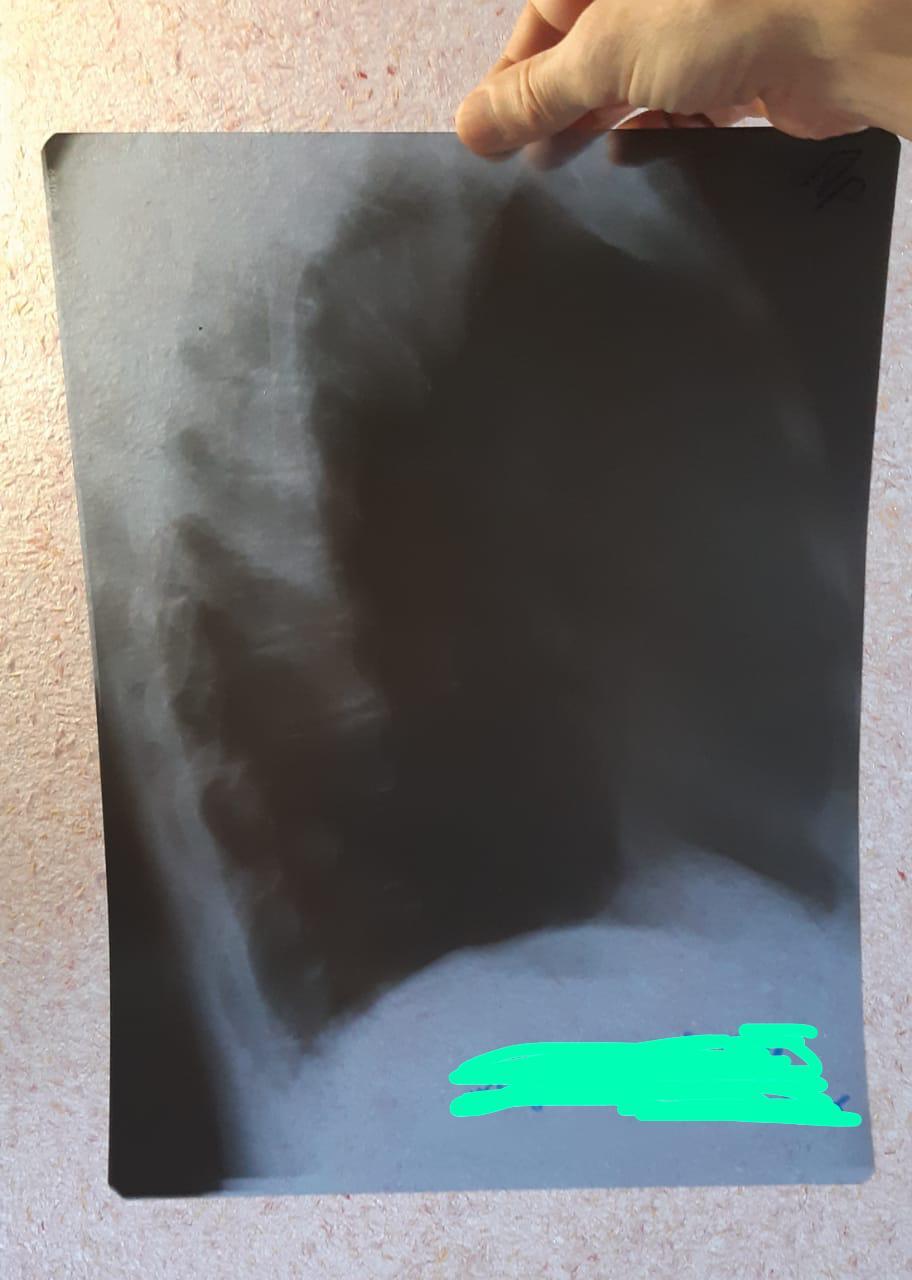

И этот рентген показал пневмонию, хотя никаких симптомов болезни не было. По скорой отвезли в больницу. Но там на снимке не нашли признаков пневмонии, кровь тоже ничего не показала. В госпитализации, в итоге, было отказано.

Признаков болезни, по-прежнему, нету. То-есть, совсем нету кашля и температуры. Создаётся впечатление, что либо рентгенолог, либо врач в приёмном покое больницы неправильно расшифровали снимки.

Собственно, вот эти снимки и справки